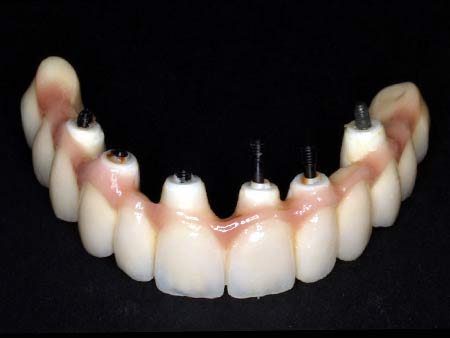

Los implantes son raíces de titanio que sustituyen a una pieza dental.Utilizamos el sistema más avanzado para colocar implantes sin necesidad de abrir la encía, con lo que disminuimos las molestias postoperatorias para el paciente, es el sistema Nobel Guide.

Así mismo existe la posibilidad de colocar una prótesis provisional el mismo día de la intervención, con lo que el paciente tiene asegurada una estética y función desde el primer día.

Otros alternativas al tratamiento: all in four, dientes en una hora, procera implant bridge, dientes de porcelana y zirconio.